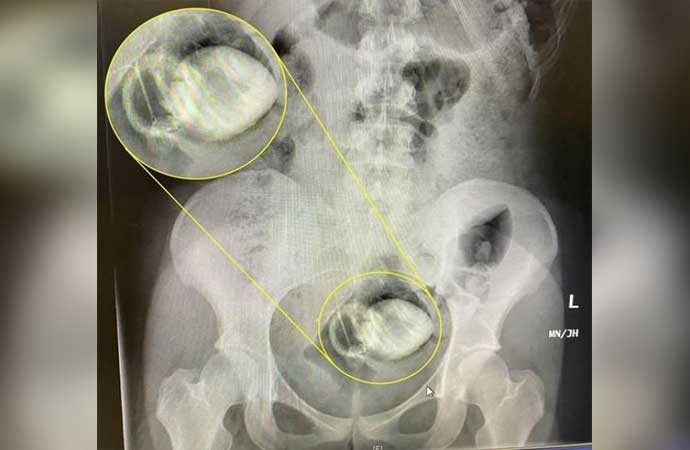

kaçan şey anal plugger gibi görünüyor. güvenliksiz kullanmamak gerek gerçekten.

dünyanın gündemine oturan akıllara durgunluk veren olay ingiltere’nin başkenti londra’da yaşandı. 20 yaşındaki rosiee sunshine isimli genç kadın, erkek arkadaşı ile görüntülü konuşuyordu. erkek arkadaşı, rosiee’den oyuncakla kendini tatmin etmesini istedi. 20 yaşındaki genç kadın, erkek arkadaşının isteğini kabul etti. sunshine, erkek arkadaşı kendisini izlerken oyuncağı makatına soktu. oyuncak makatında sıkışıp kaybolunca kadın, tekrar çıkaramadı. genç kadın mutfağa gidip maşa ile çıkarmak istedi. erkek arkadaşı kendisine daha fazla zarar verebileceğini söyleyip kendisine engel oldu.

tüm çabalara rağmen oyuncağı çıkarmayan rosiee sağlık ekiplerini aradı. genç kadın, eve gelen sağlık ekipleri tarafından hastaneye kaldırıldı. hastanede yapılan operasyon sonrası oyuncak sıkıştığı yerden çıkarıldı. doktorlar, yaptıkları açıklamada, insanların her oyuncağı kullanmamaları konusunda uyardı.